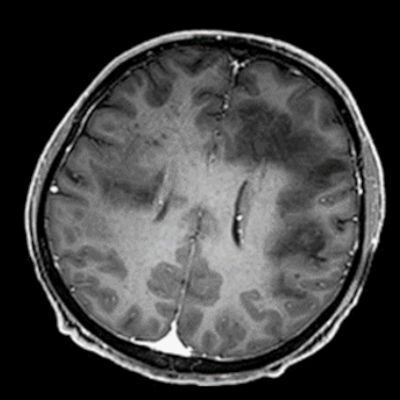

- Bilateral asimetrik subkortikal ve derin beyaz cevherde T1 ağırlıklı görüntülerde belirgin hipointens (oklar), T2A görüntülerde hiperintens (oklar), gri cevhere bakan kesimi düzgün (oklar), DAG’de hiperintens (ok) lezyonlar izlendi. Lezyonlarda T2/FLAIR uyumsuzluğu vardı (ok). Serebellar beyaz cevherde dentat nukleusu koruyan hilal işareti görüldü (ok başı). SWI sekansta sol motor kortekste hipointens kronik glioinflamatuar reaksiyon ile uyumlu sinyal değişikliği izlendi (ok başı).

- Çoğunlukla subkortikal beyaz cevherde ve U fiberlerde, asimetrik, genelde kitle etkisi yapmayan ve kontrastlanmayan demiyelinizan lezyonlar görülür. Korteks ve derin gri cevher tutulumu daha nadirdir.

- PML lezyonları, T1A görüntülerde belirgin hipointenstir. Gri cevhere bakan yüzleri keskin olup T2/FLAIR uyumsuzluğu önemli özelliğidir.